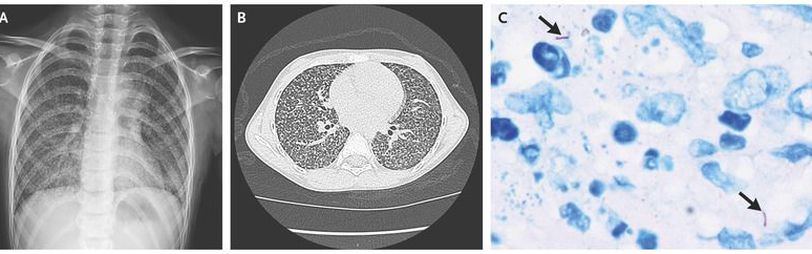

A previously healthy 8-year-old girl presented to the hospital with a 3-month history of dry cough and persistent fevers. A chest radiograph (Panel A) and a subsequent contrast-enhanced computed tomographic (CT) scan (Panel B) showed a diffuse, miliary (i.e., millet seed–like) pattern of uniformly sized, small nodules throughout both lungs. The soft-tissue window (not shown) revealed necrotic-appearing mediastinal lymph nodes. A tuberculin skin test and an interferon-γ release assay were positive, and a sputum acid-fast bacilli smear was negative. Cultures were obtained from multiple sources, including sputum, bronchoalveolar lavage, and cerebrospinal fluid. During the wait for the culture results, empirical first-line treatment for tuberculosis was initiated; however, the patient’s condition did not improve after 2 months of therapy. Because the cultures remained negative, a lung biopsy was performed with video-assisted thoracoscopy; a hematoxylin and eosin stain of the biopsy specimen showed caseous necrosis, and an acid-fast stain was positive for bacilli (Panel C, arrows). Drug-resistant tuberculosis was suspected. Because the results of tests to confirm drug resistance can take weeks to return, treatment was empirically changed to a regimen that is standard for drug-resistant tuberculosis in the region. The patient’s temperature returned to normal within 2 weeks after initiation of this treatment regimen, and repeat CT images at 2 months showed improvement. When the results of the drug-resistance tests were returned, isoniazid-resistant tuberculosis was confirmed.